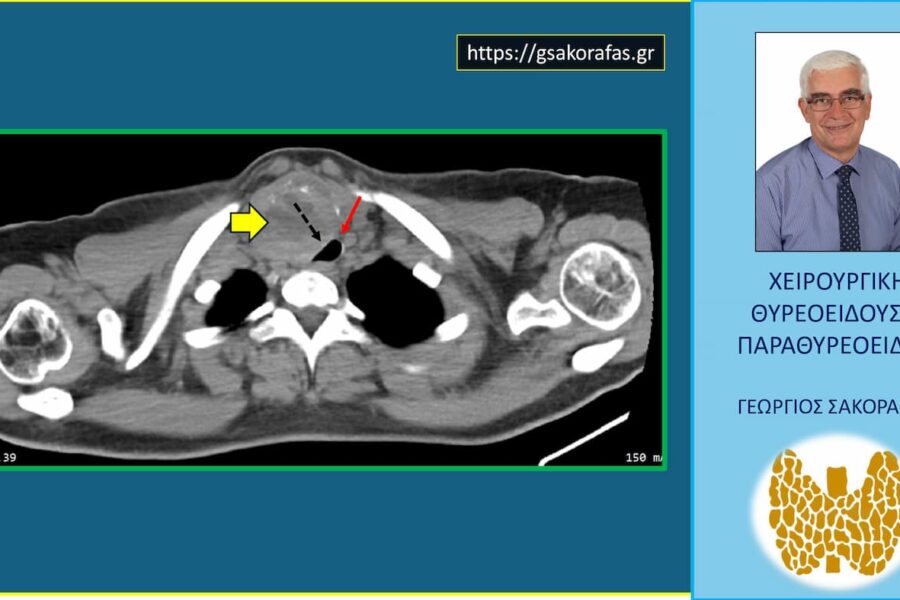

Όζοι θυρεοειδούς και συμπληρωματική θυρεοειδεκτομή (completion thyroidectomy) – με αφορμή ασθενή μας Παρουσίαση ασθενούς Αιτία…